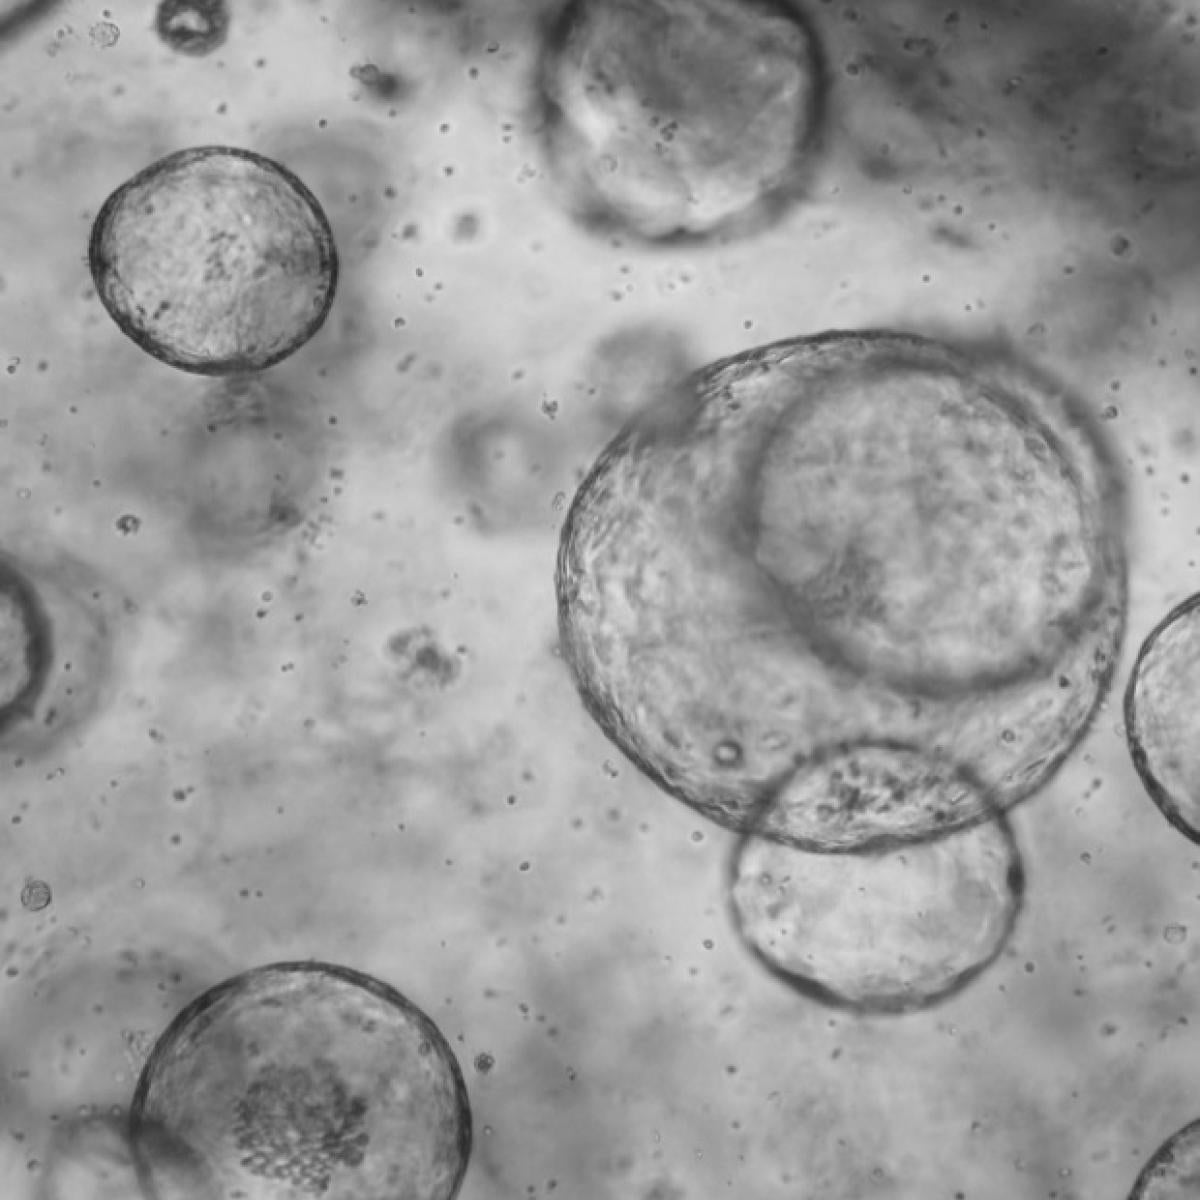

Quijada's research focuses on understanding the cell and molecular signaling programs that control blood vessel formation, or angiogenesis, to promote regenerative-based repair of the adult heart. She investigates the roles cardiac mural cells and fibroblasts play in regulating vessel formation and stability as the coronary vasculature develops.

A key area of study is the epicardium, the heart's outer layer, which plays a crucial role in cardiac cellular patterning and morphogenesis. She examines how the epicardium communicates with the developing coronary blood vessels, guiding cellular maturation and differentiation through chemical signaling mechanisms. Using mouse models and advanced techniques like single-cell transcriptomic sequencing, Quijada uncovers novel epicardium-directed guidance cues required for blood vessel specification and maturation.

The adult heart, unlike the fetal heart, struggles to grow new blood vessels after injury, leading to declining heart function. Applying insights from her developmental studies, Quijada investigates how factors secreted by the epicardium might promote blood vessel growth and repair in the adult heart after myocardial infarction.